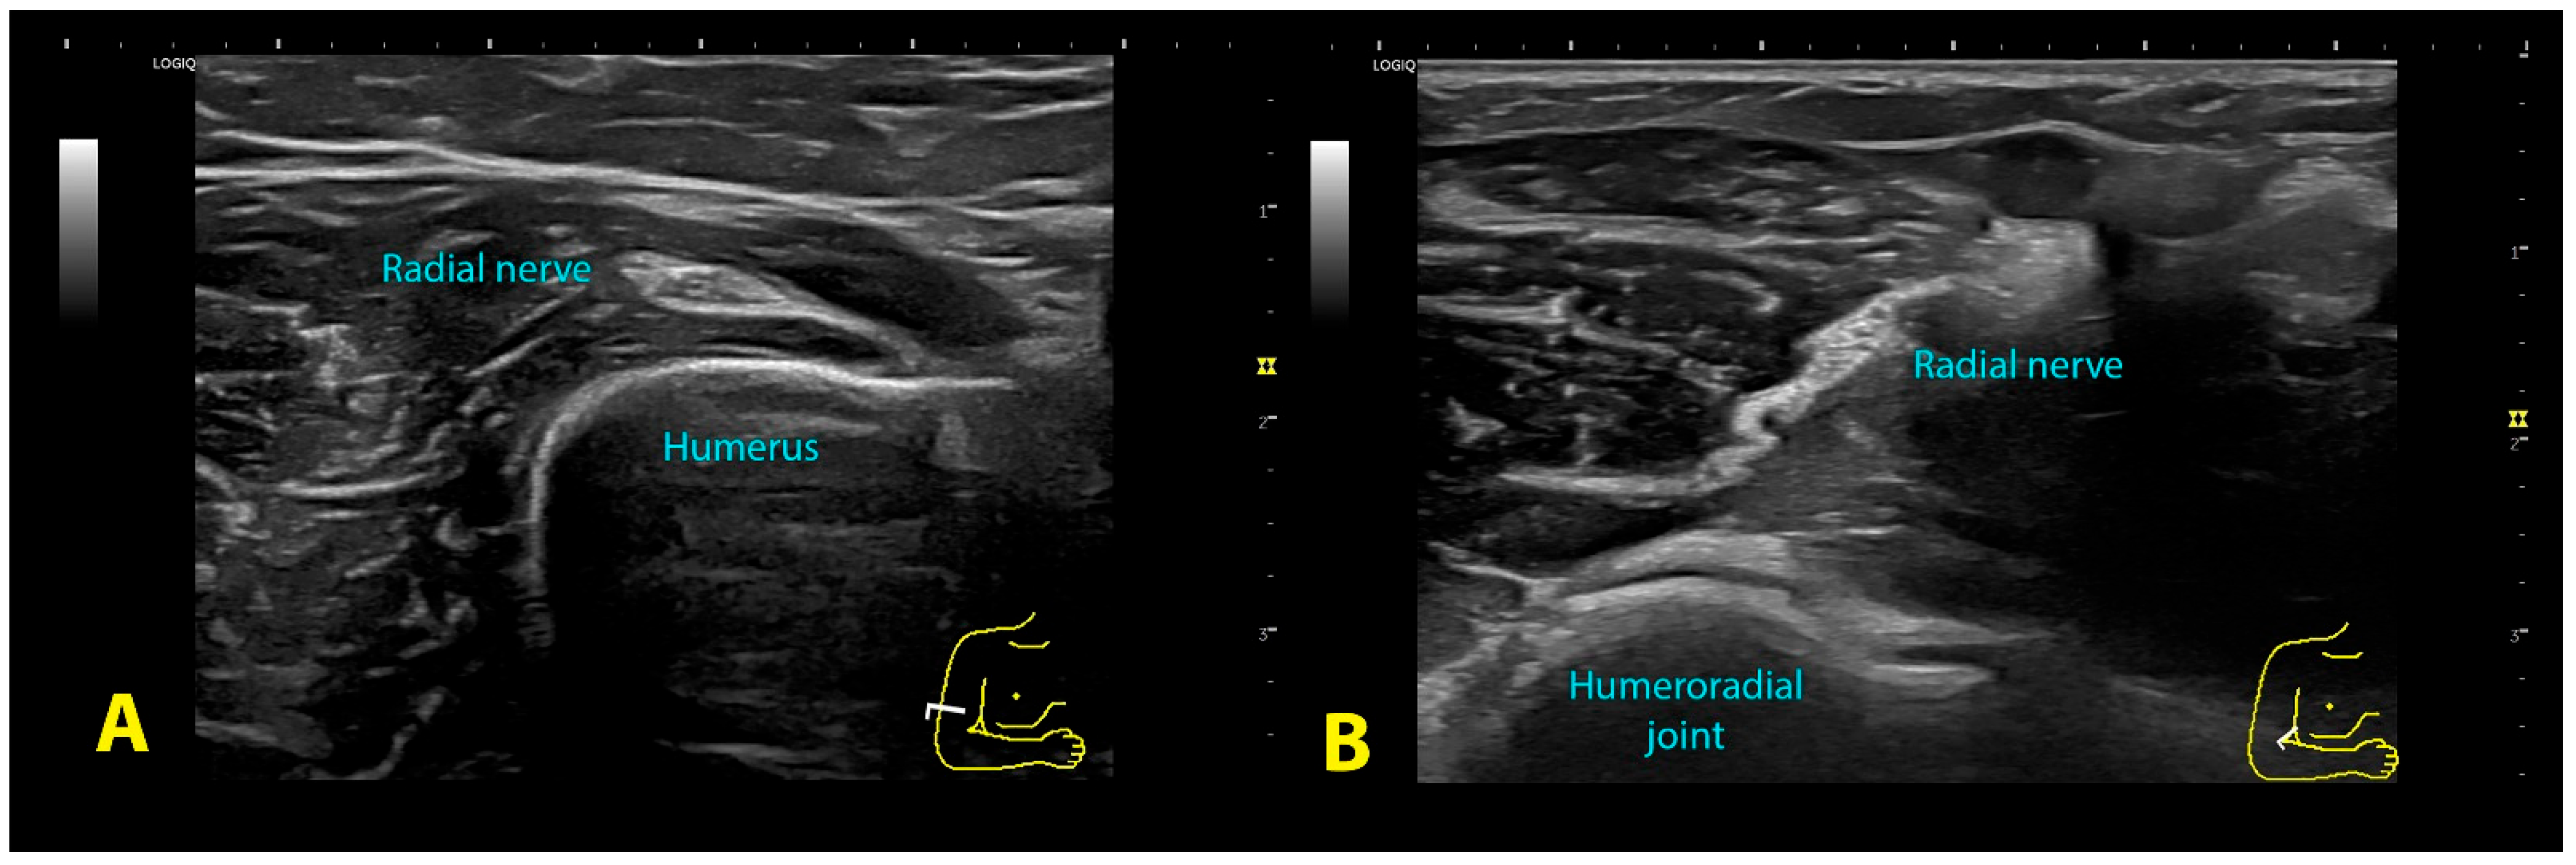

Figure 3.

Ultrasound image of the radial nerve at the spiral groove (A) and the antecubital fossa (B).

Spiral groove: The patient was sitting with their arm resting on table, elbow flexed 90° with the forearm pronated and hand relaxed resting on table. The probe was placed transverse to the axis of the arm, on the lateral aspect of the distal third of the humerus (Figure 2A), searching for the intermuscular septum and the exit of the nerve from the radial groove (Figure 3A).

Antecubital fossa: The patient was sitting with the arm resting on the table, the elbow extended and the forearm supinated. The probe was placed transverse to the axis of the arm at the level of the anterior aspect of the elbow flexure, observing the elbow joint space (Figure 2B). The nerve lies between the brachioradialis muscle and the anterior brachialis muscle (Figure 3B). The radial nerve was imaged before it divided into its two branches; therefore, sometimes it was necessary to move the probe 1–2 cm above the elbow joint line.